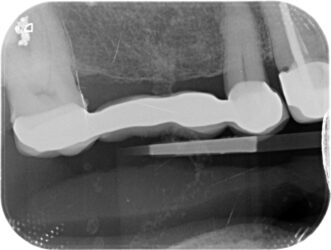

Hi I have an implant bridge case to restore. Pt is in his 80s. I have just been restoring single units before this and would love some help/advice about how to proceed. The initial idea was just to scan, which I’m comfortable doing. But I have learned that the scanner may not be so accurate for larger cases like this. I will order a special tray first of all.

Traditional impressions for the lab to scan if needed and bite with wax rim. I find that to be most predictable.